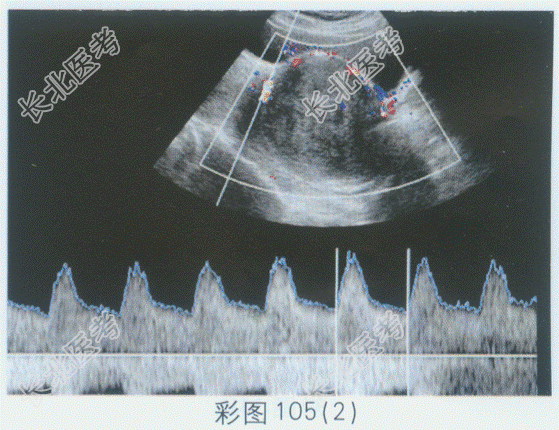

- 单项选择题临床资料:女性患者, 42岁,自述下腹坠胀, 月经量增多3年余。

超声综合描述:子宫前位, 宫颈部可见7.8cm×7.2cm低回声区,边界清晰, 形态规则,内回声不均匀, 呈漩涡状,向外突起, CDFI:周边可见少许血管绕行, 呈动脉血流频谱。见下图及彩图105。

超声提示: A、阔韧带肌瘤

B、子宫颈肌瘤

C、子宫颈妊娠

D、子宫颈癌

E、子宫腺肌病